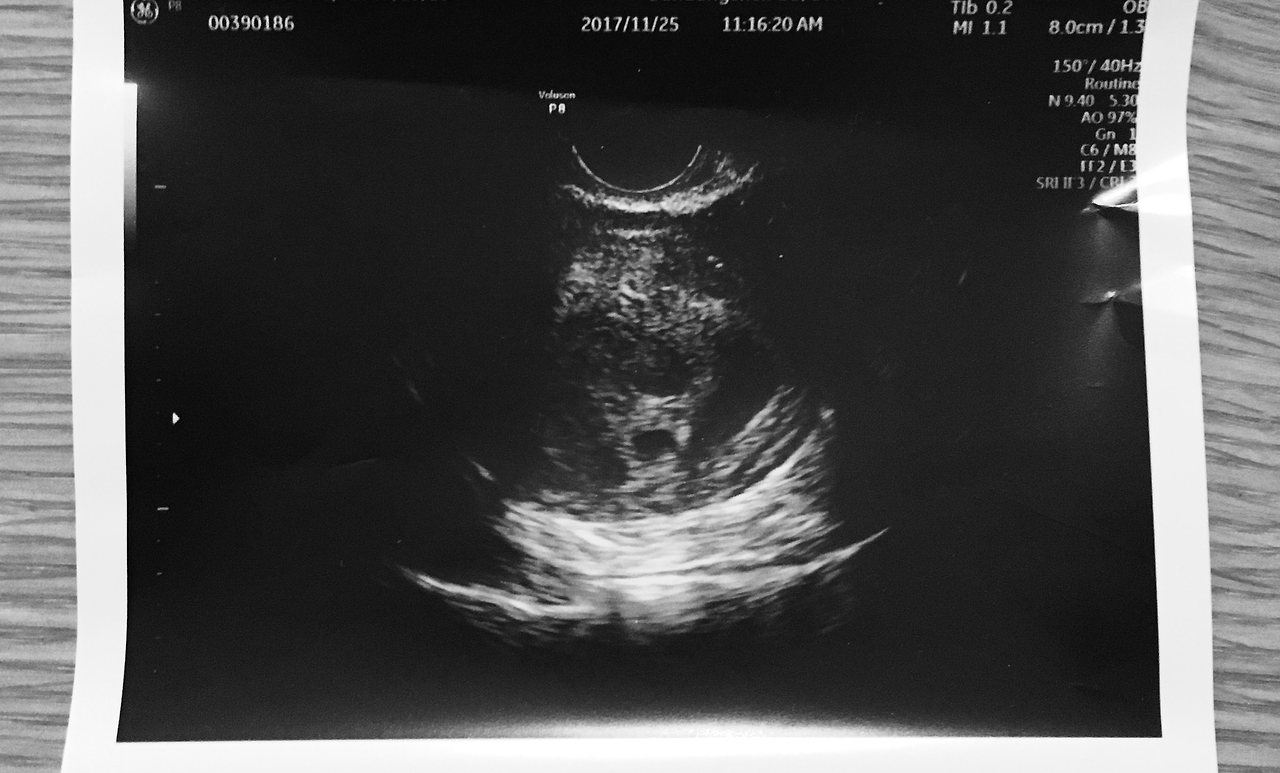

임신을 해야겠다는 결심을 한 건 그 와중이었다. 엄마가 중환자실에 머물 때였고, 나를 제대로 알아보지도 못할 때였다. 30분 간 가능한 면회를 위해 먼 길을 달려가 엄마 얼굴을 보고 집으로 돌아왔다. 옷을 갈아입으러 들어간 안방은 암흑이었다. 그냥 침대에 드러누워버리고 싶은 처진 마음과 몸을 겨우 일으켜 가장 가까이에 있는 스위치를 눌러 전등을 켰다. 안방 화장실에 불이 들어왔다. 문틈으로 새어들어오는 불빛에 의지해 침대에 던져두었던 실내복을 주섬주섬 입으려는데, 느닷없이 아이를 갖고 싶어졌다. 생전 처음 느끼는 임신에 대한 강한 열망이었다. 곧바로 평소 사용하던 생리 주기 어플을 열어 가임 기간을 확인했다. 퇴근하고 돌아온 남편에게 아이를 가져야겠다고 말했다.

아픈 엄마와 임신 결심 사이에 어떻게 인과 관계가 형성되었는지 그때도 지금도 알지 못한다. 육신이 얼마나 빠르게 무너질 수 있는지 엄마의 몸을 통해 목격하고 있을 때였다. 엄마와 가족들 앞에서는 희망에 대해 말했지만, 속으로는 비명을 지르며 하루하루를 보내고 있었다. 모든 것이 뒤숭숭하던 때에 그렇게 큰 결정을 내릴 수 있다니, 엄마가 아픈데 아이를 갖겠다니, 불경하게 느껴지기도 했다. 하지만 결심은 확고했다. 결국 두 번의 시도 끝에 임신이 되었다.

아기집을 지어놓았다